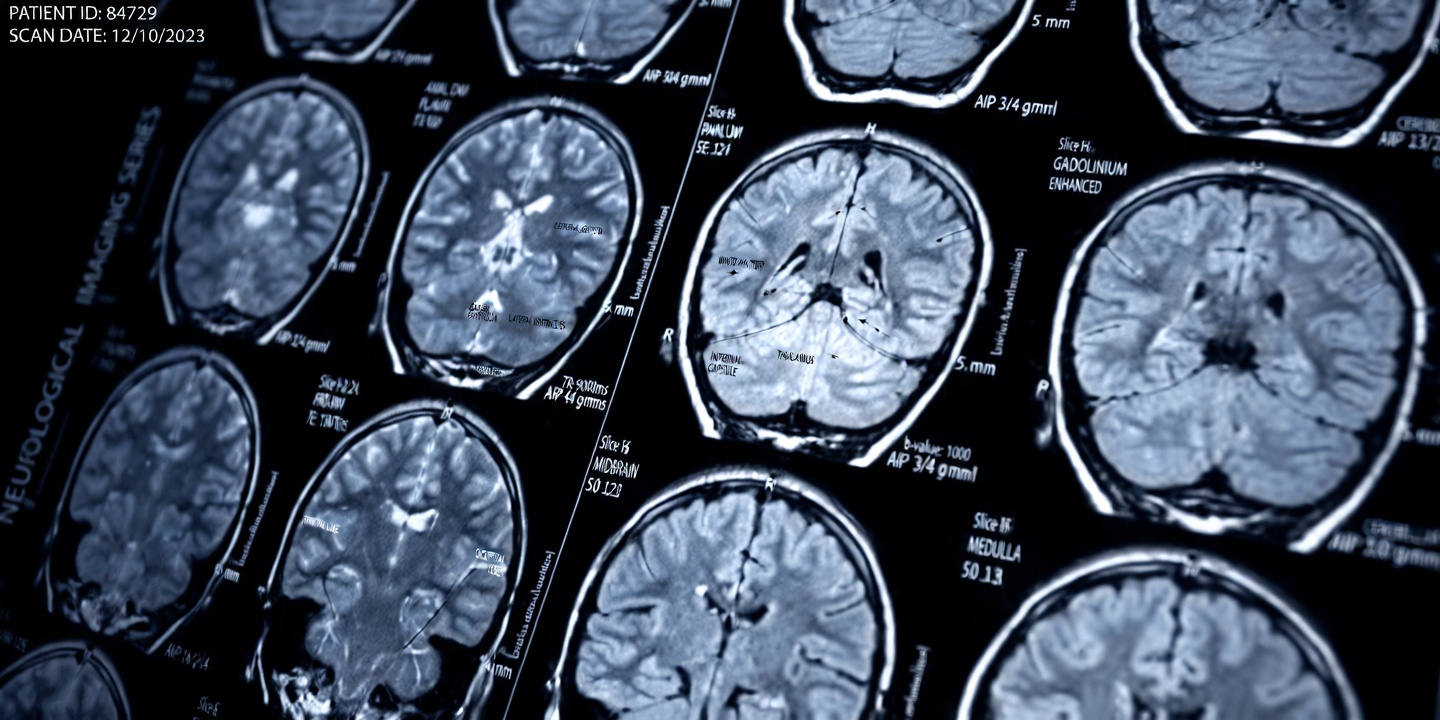

What makes lacunar strokes particularly challenging is that each individual event may be small. Yet over months or years, repeated injury can damage regions such as the basal ganglia and thalamus, leading to noticeable declines in mobility, coordination, bladder control, and cognitive function.